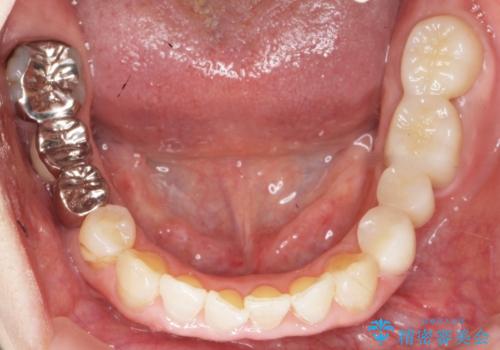

手術後に根管治療を行い、歯肉と骨の治癒を十分に待った後ブリッジによる補綴治療を行いました。

ご希望通り歯を抜かずに残すことができ、喜んで頂けました。

セルフメンテナンスしやすいよう、ブリッジと歯ぐきの間に歯間ブラシを通すことができるように作製しています。

咬合関係により奥歯の負担が大きいため、今後も注意深く経過観察していく予定です。